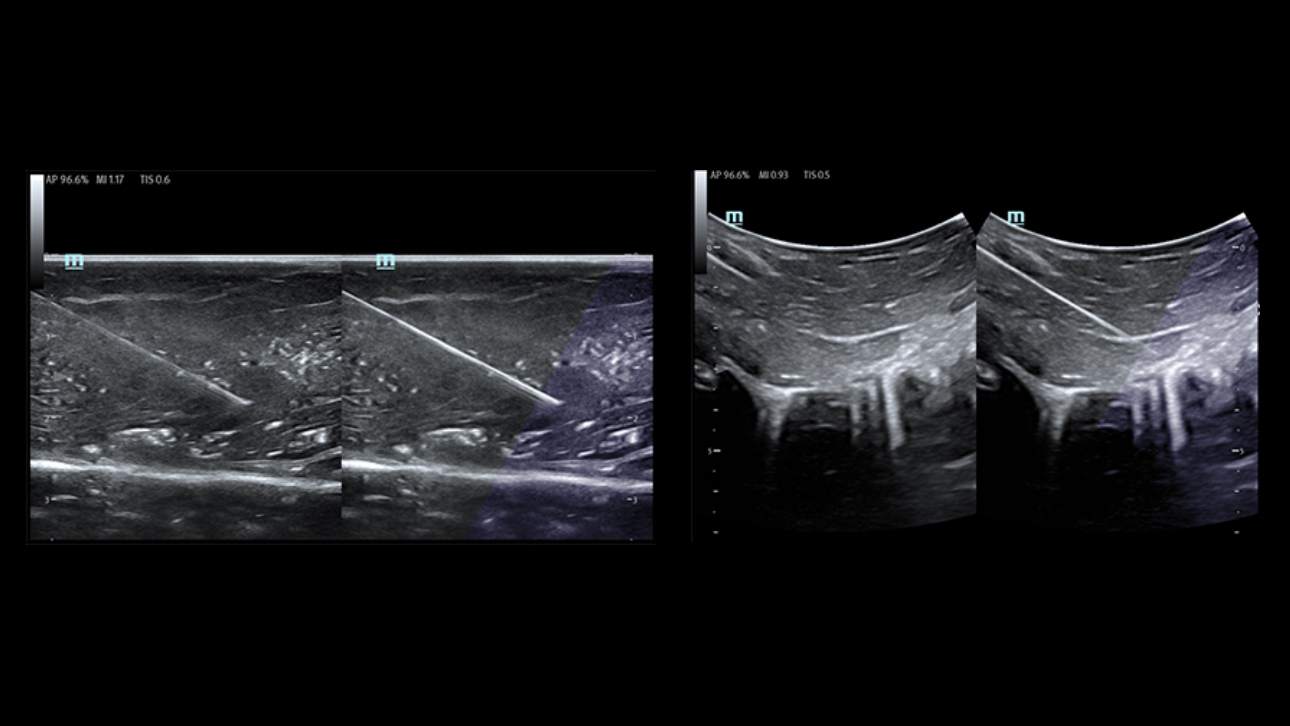

SoluciĂłn de punciĂłn para un solo operador